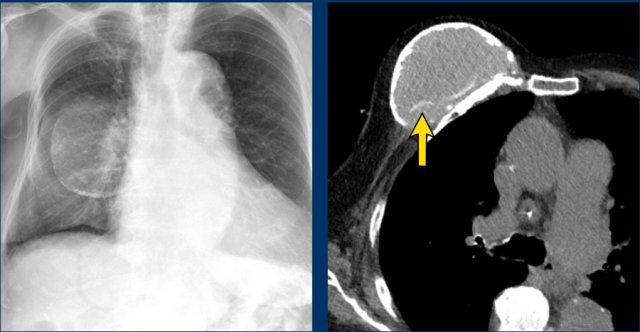

X-Ray and CT

Chest X-Rays and CT do not play a role in examining breast implants.

Sometimes they can be detected on X-rays for instance when there are capsular calcifications or when a filling valve of an expandable prosthesis is seen (arrow).

Also on CT sometimes complications can be seen, but usually CT does not give adequate information about the integrity of the prosthesis.

The chest film shows capsular calcifications in a medially displaced breast implant, which is not parallel to the breast contour.

The CT of the same patient shows also calcifications at the posterior side not following the contour of the implant indicating intracapsular rupture (arrow).